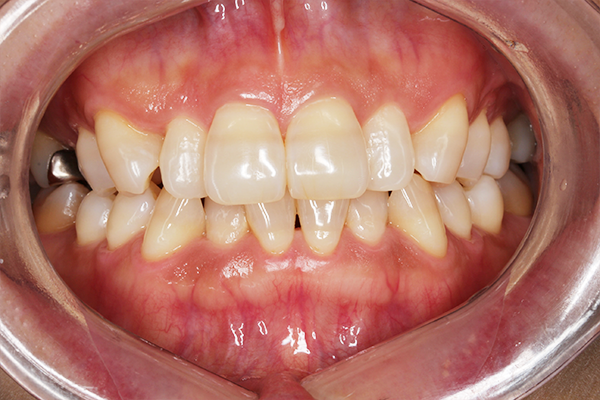

術前

術後

虫歯治療費+オフィスホワイトニング施術費(38,500円)

主訴 たばこのヤニなど全体的にきれいにしたいと来院。

むしば治療とオフィスホワイトニングを2回行い全体的に白くすることができた。

治療期間:1か月

副作用・リスク:一時的に知覚過敏の症状が出る可能性あり